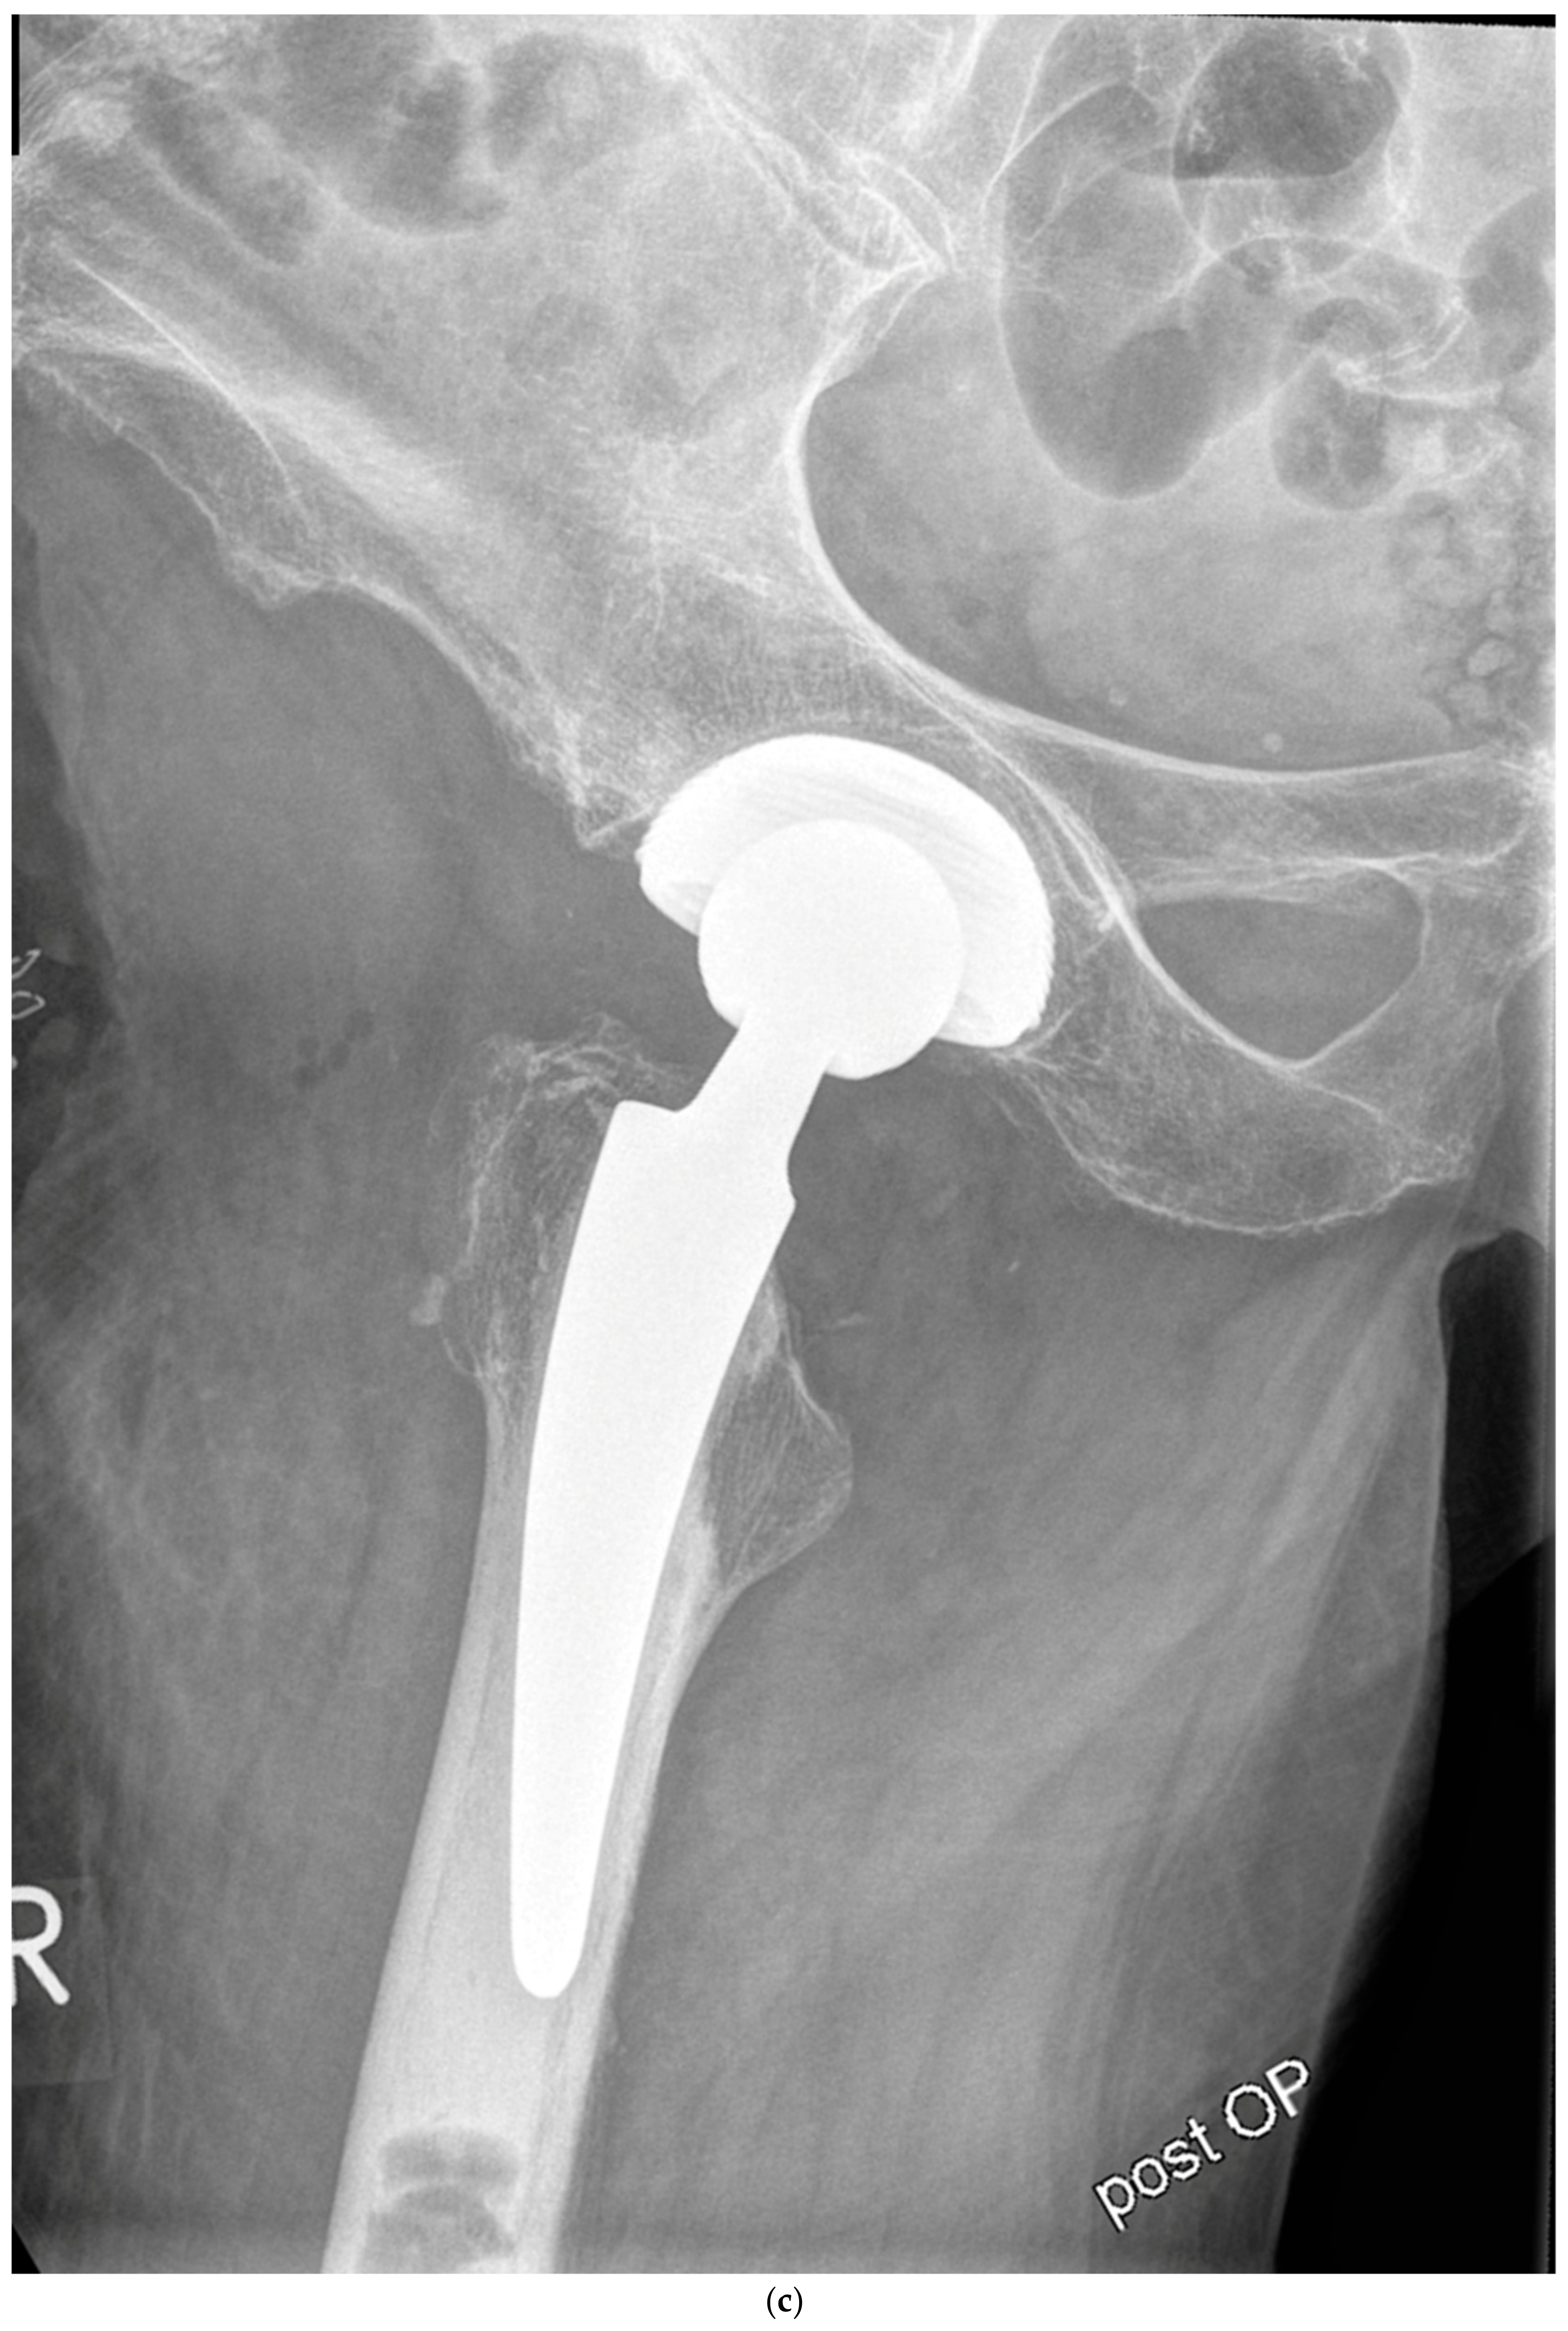

The mean HHS increased from 49.4 ± 13.9 preoperatively to 93.6 ± 6.9 at the final follow-up. No pain was reported by 19 patients at the final follow-up, with only occasional slight pain in one patient. The mean UCLA score increased from 3.5 ± 1.5 preoperatively to 5.1 ± 1.9 at the one-year follow-up. The mean HOOS-PS score increased from 44.2 ± 22.1 preoperatively to 60.0 ± 28.6 at the one-year follow-up. The FJS score was 68.3 ± 14.6 at the one-year follow-up. One patient experienced leg shortening of 10 mm. Periarticular ossification Brooker 1 was identified in three patients. One patient experienced axial subsidence of 2 mm. There were no postoperative infections. No radiolucent lines were observed, and none of the patients presented with osteolysis. A representative case is presented. Preoperative planning facilitated the achievement of anatomic restoration, as depicted in Figure 2. Figure 3 and Figure 4 demonstrate the correct postoperative positioning of the femoral stem and a complete cement mantle.

Figure 4.

(a) Case #3: Osteoarthritis, female, 81 years old, preoperative planning. (b) Correct implant position 1 week postoperatively. Homogeneous cement mantle.